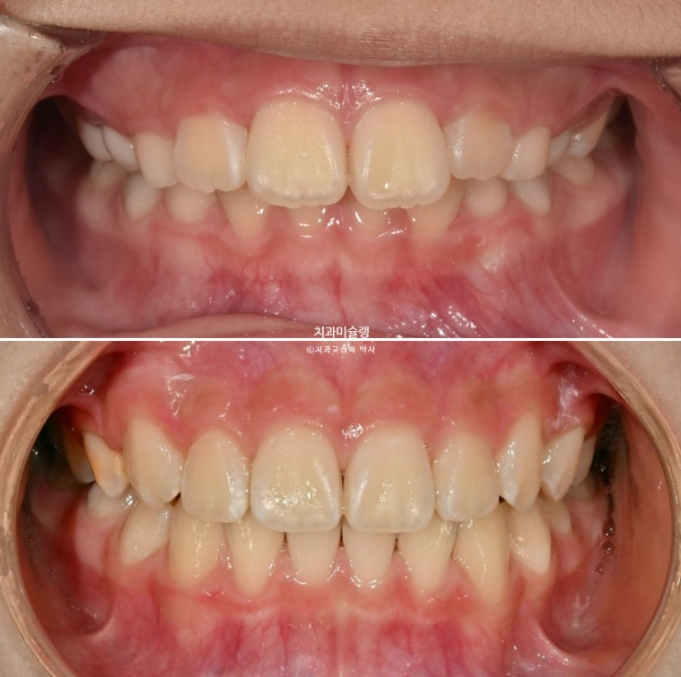

이제 전 후 비교 볼게요

23.10~25.11

과개교합과 중심선 불일치의 개선

완성된 교합은 1급 교합관계를 보입니다.